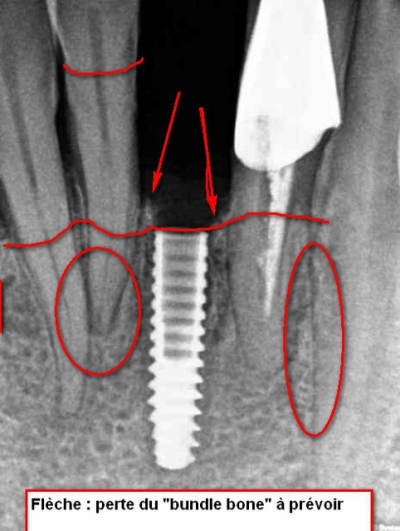

mais que fais-tu de l'os autour de cet implant avec la paro ?

Le bundle bone va fondre suite à la pose.

Place nous une radio dans 1 an.

Le bundle bone qui fond... c'est plus au buccal de l'implant qu'au interproximale...de toute facon cet implant n'est pas dans une zone esthétique high lip line etc de 13 à 23. On connait le traitement idéal mais on doit dealer avec des patients....